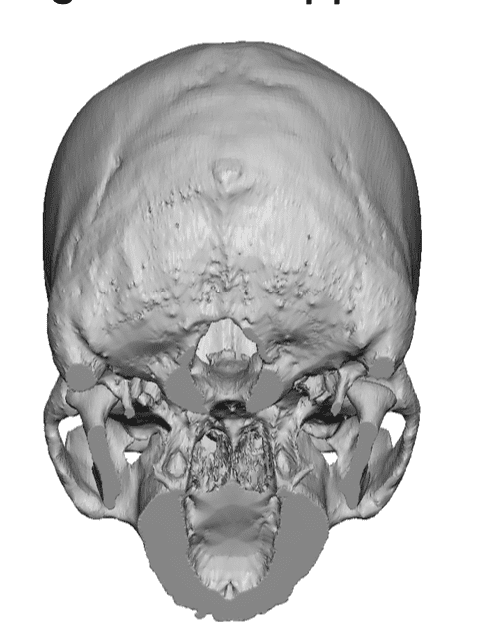

Desire for an improved head shape so that it looks rounder and not so peaked or sloped.

Placement of custom skull implant for parasagittal augmentation to create a rounder head shape. An example of what appears to be a high sagittal crest that is really low parasagittal skull areas.

Desire for an improved head shape so that it looks rounder and not so peaked or sloped.

Placement of custom skull implant for parasagittal augmentation to create a rounder head shape. An example of what appears to be a high sagittal crest that is really low parasagittal skull areas.